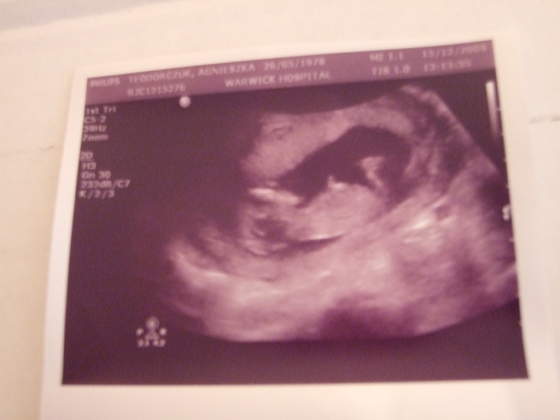

Super maluszki:-)